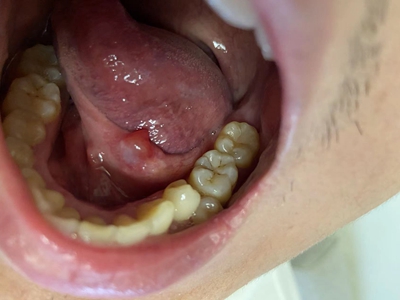

舌下腺囊肿舌头底下的筋旁边长个球形疙瘩图

舌下腺囊肿位于舌系带一侧的口底黏膜下,表现为表面光滑的球状大疙瘩,常继发感染导致局部肿胀、疼痛,呈进行性增大,并越过舌系带在对侧隆起。